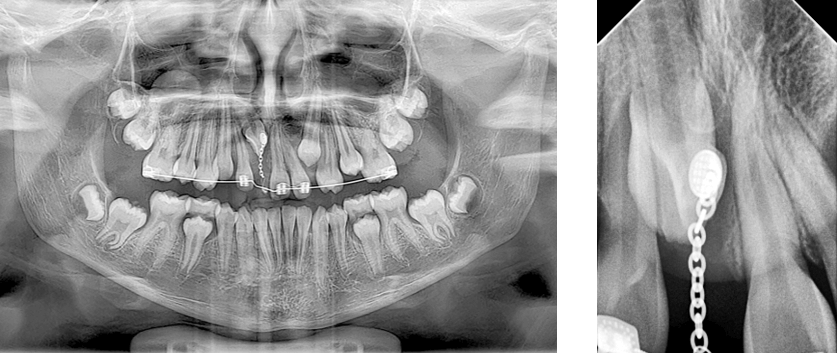

Posterior a la cirugía se realizó una radiografía panorámica y periapical con técnica de bisectriz como método de control para el tratamiento (Fig 14 y 15 ) y la activación del botón de tracción con el arco 16x22 niti superior (Fig 16).

Fig 14 y 15. Rx periapical N1 con botón y cadeneta y Rx panorámica

Fig 16. Fotografía de activación del botón de tracción